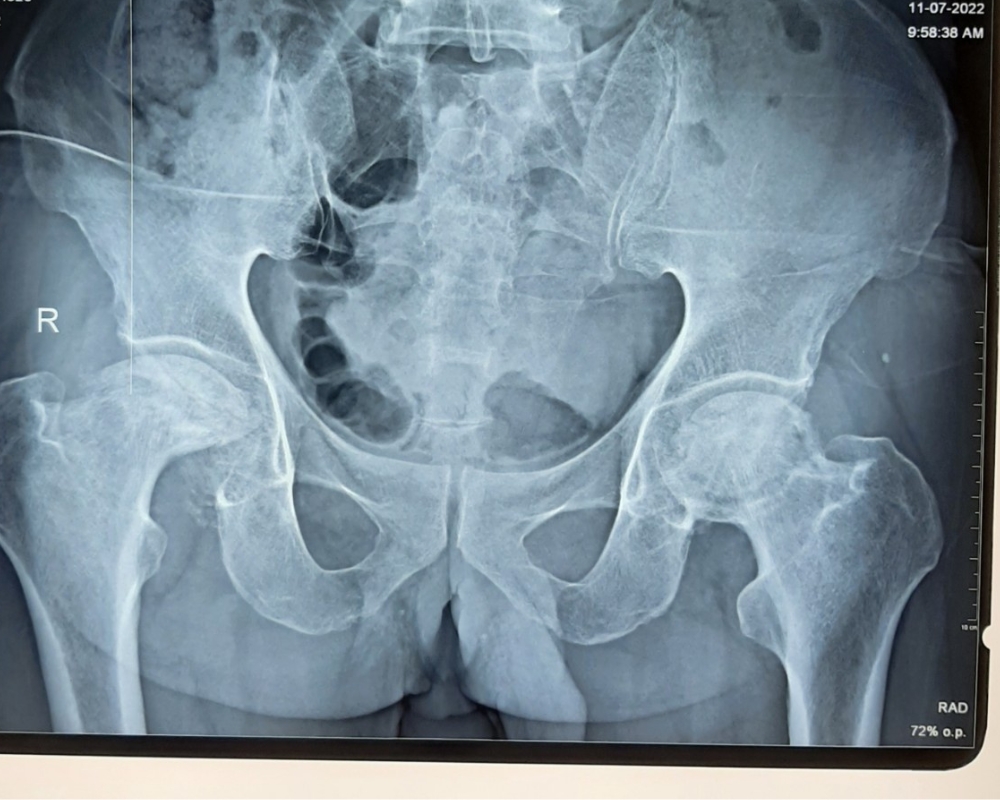

Chẩn đoán bệnh thoái hóa khớp háng

Chẩn đoán bệnh thoái hóa khớp háng thường được thực hiện thông qua một số phương pháp sau:

- X-quang: X-quang được sử dụng để xác định mức độ thoái hóa của khớp và xác định rõ hơn về sự hư hại của xương và cấu trúc khớp.